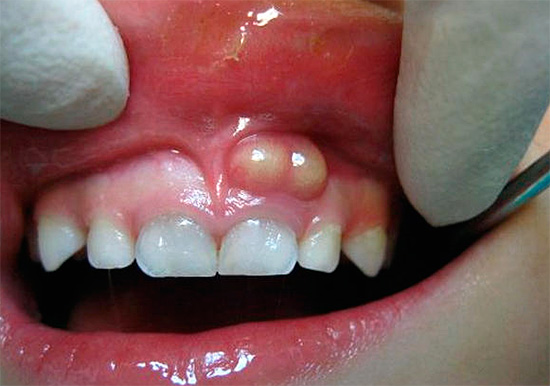

Nella pulpite ipertrofica cronica, il dente, di regola, è leggermente preoccupato. Il sintomo principale in questo caso è il dolore doloroso durante la masticazione di cibi solidi e raramente da irritanti della temperatura. A volte si osserva sanguinamento del dente durante il pasto, che è associato alla crescita nella carie cavità della polpa del tipo di "carne selvatica" e alla sua lesione meccanica. È questo sintomo di polmonite cronica che spesso spaventa una persona, costringendola a cercare aiuto alla fine.

Se c'è un messaggio con una cavità cariata e compaiono dolore e sanguinamento quando si sondano con una sonda acuta, allora con un alto grado di probabilità è cronico pulite fibrosa. Con un cambiamento nel colore dei denti, l'aspetto di un'ombra grigia, con una grande quantità di tessuto cariato ammorbidito nella cavità del dente, quando il "nervo" viene parzialmente distrutto e il dolore si verifica solo quando si sondano i canali, allora è molto probabilmente una polpite cranica cronica. La comparsa di tessuto troppo cresciuto all'interno della cavità in combinazione con l'indolenzimento quando lo sondano il più delle volte indica una polpite ipertrofica cronica.

Se nel trattamento della pulpite cronica o delle sue esacerbazioni c'è un riempimento incompleto dei canali o il loro riempimento eccessivo (rimozione del materiale all'apice), immediatamente o dopo un po '(da un giorno a un anno o più) compaiono sintomi corrispondenti alla periodontite nell'esacerbazione. In questo caso, possono esserci spesso dolori acuti, l'incapacità di toccare il dente anche con la lingua, la natura pulsante del dolore e in alcuni casi, dopo qualche tempo, possono verificarsi gonfiore della mucosa nella regione dell'apice della radice del dente.

Quando uno strumento viene rotto nel canale, il dente potrebbe non manifestarsi a lungo, ma prima o poi l'infezione nella sezione della radice "non pulita" e non sigillata causerà un processo purulento nel canale con la formazione di un "flusso", o il processo avrà una forma cronica con formazione al meglio fistole (dotti che si aprono sulle gengive, attraverso le quali il pus dalla radice del dente viene secreto nella cavità orale) e, nel peggiore dei casi, la formazione di sacche purulente - cisti.